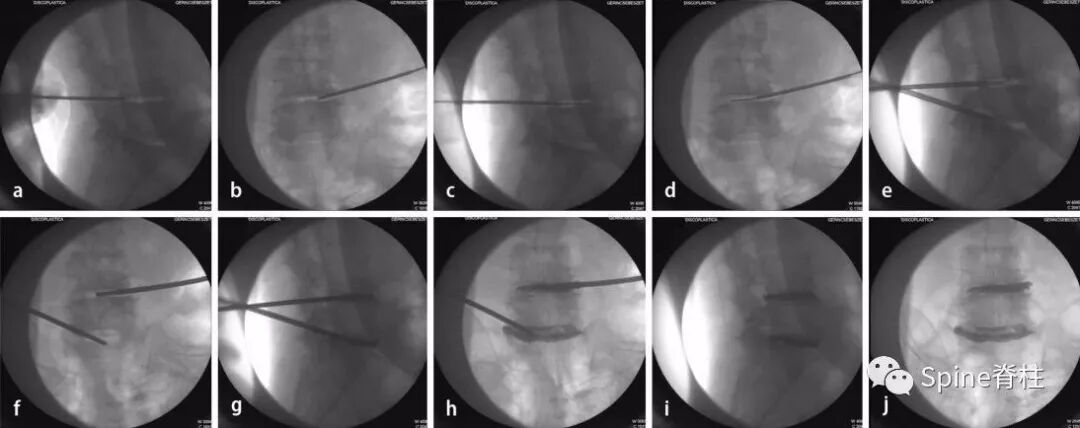

A:俯卧位,髋关节伸展,以增加腰椎前凸和椎间盘间隙。

B:经皮透视下放置Jamshidi针。

C:在肌电图监护下穿刺并注射。

D:缓慢注射骨水泥。

经椎弓根外入路(安全三角)

经椎弓根入路